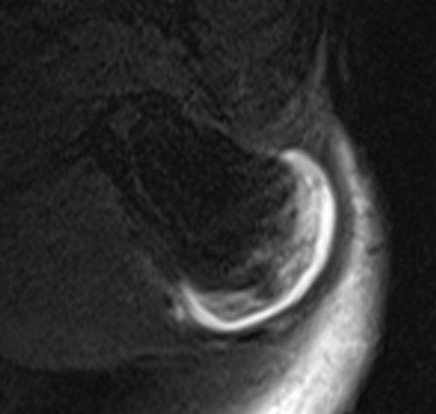

MRI

Cartilage cap iso-intense with hyaline cartilage

Suspicious features

- growth after maturity

- increased thickness of cartilage cap on CT / MRI - > 2 cm

- increasing pain

- increased calcification / bony erosion / lytic areas on xray

- septal enhancement after MRI with gadolinium

- MRI / CT of 64 benign osteochondromas and 34 secondary chondrosarcomas

- cartilage cap 2 cm or more 100% sensitive and 98% specific for secondary chondrosarcoma